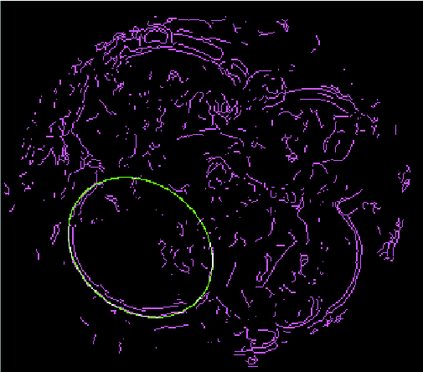

We present a novel method for identification of the boundary of embryonic cells (blastomeres) in Hoffman Modulation Contrast (HMC) microscopic images that are taken between day one to day three. Identification of boundaries of blastomeres is a challenging task, especially in the cases containing four or more cells. This is because these cells are bundled up tightly inside an embryo's membrane and any 2D image projection of such 3D embryo includes cell overlaps, occlusions, and projection ambiguities. Moreover, human embryos include fragmentation, which does not conform to any specific patterns or shape. Here we developed a model-based iterative approach, in which blastomeres are modeled as ellipses that conform to the local image features, such as edges and normals. In an iterative process, each image feature contributes only to one candidate and is removed upon being associated to a model candidate. We have tested the proposed algorithm on an image dataset comprising of 468 human embryos obtained from different sources. An overall Precision, Sensitivity and Overall Quality (OQ) of 92%, 88% and 83% are achieved.